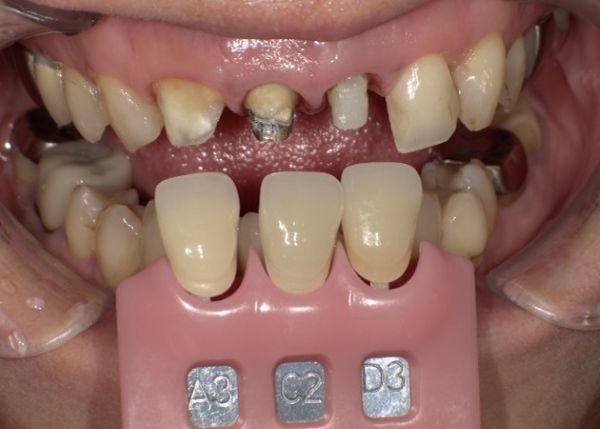

型取り、色合わせのための写真撮影を行い最終補綴へ移行しました。

色調に関しては、写真を多数撮影して、提携ラボ歯科技工士さんへお送りし、色調の再現をお願いしております。

使用カメラに関しても技工士と同じものを使用する事で、色の誤差などを最小限に減らすよう工夫しております。